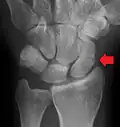

A subtle scaphoid fracture -

A more obvious scaphoid fracture on a scaphoid view X ray -